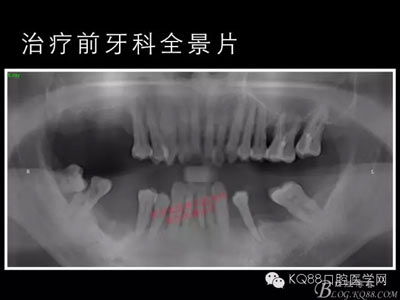

下面的種植病例是為患者提供全口牙齒治療修復(fù)完整過(guò)程的下頜部分,我們門(mén)診和患者共同配合下目前取得了較好的修復(fù)效果,即將開(kāi)始的上頜牙齒治療修復(fù)過(guò)程仍然艱辛。